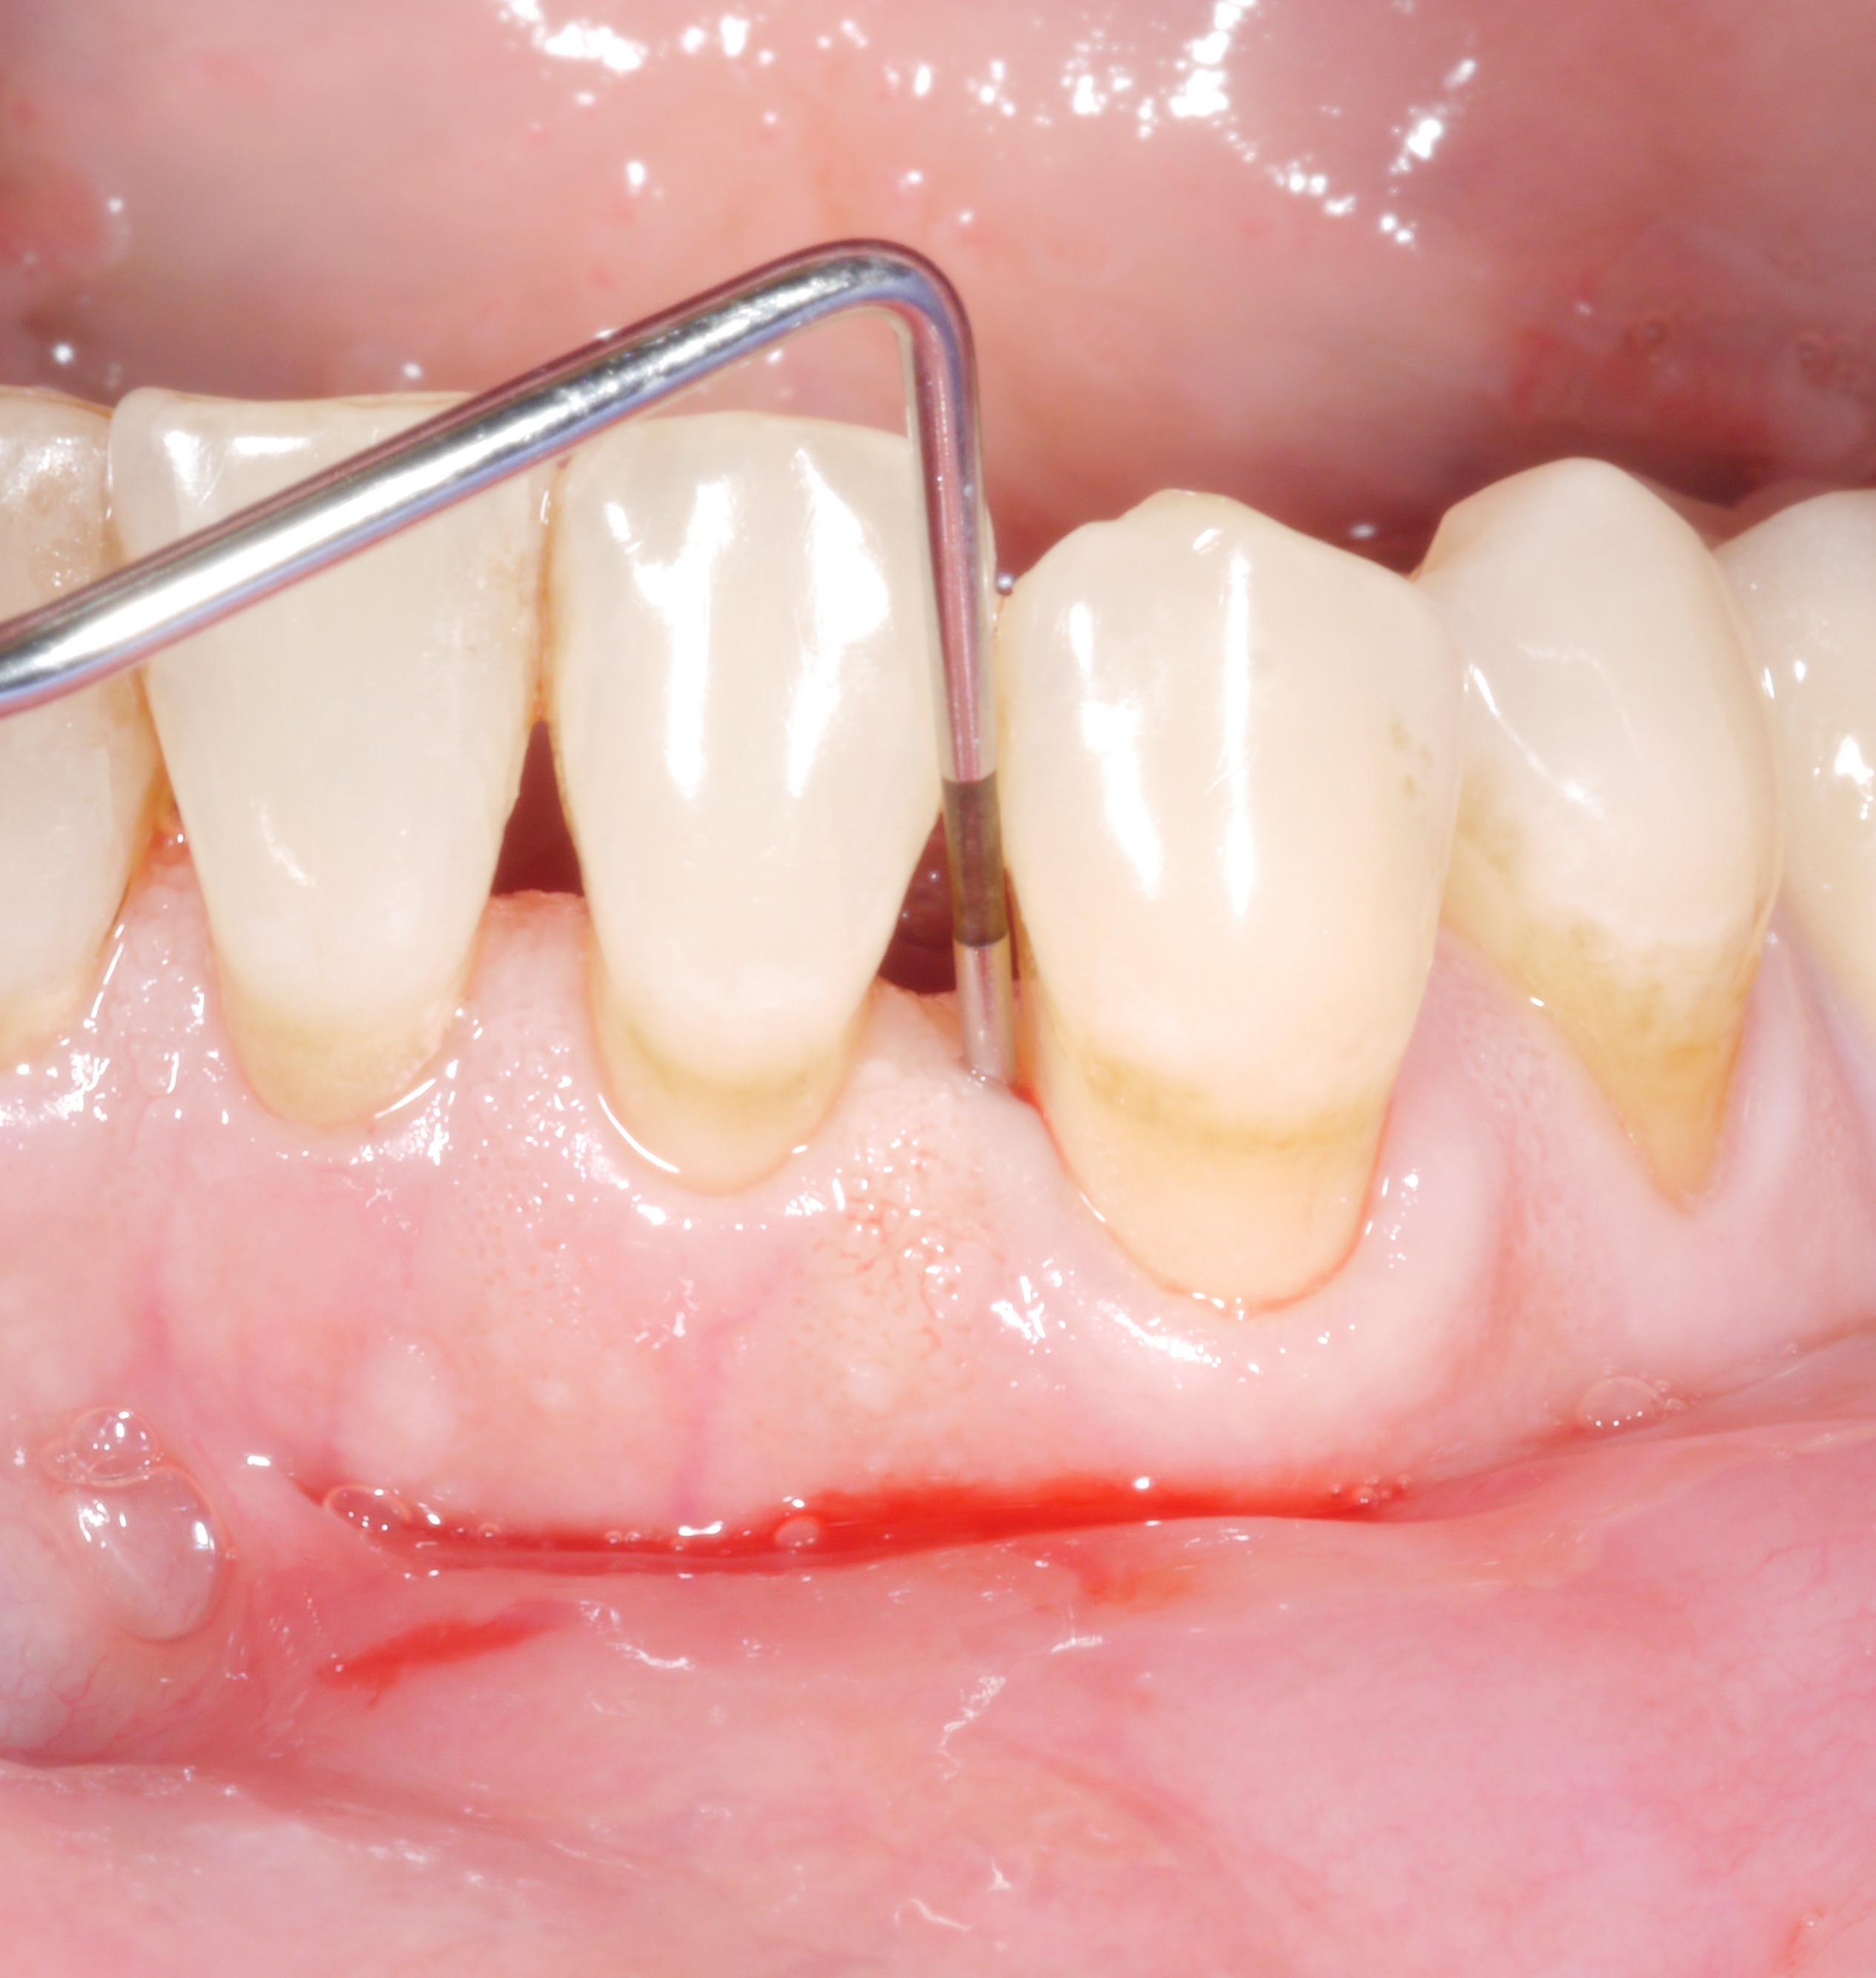

It is a situation we are all too familiar with: following the active phase of treatment, nearly all the patient’s teeth are now unaffected by increased pocket probing depths. However, there are still 1 or 2 places where the treatment goal has unfortunately not been achieved. The following thought might arise: “how bad can it be? A single pocket of 6 or 7 mm – surely that can’t make a big difference?

However, dentists should not rush to say they are content with residual pocket probing depths. This is because even individual residual pocket probing depths of more than 4 mm constitute a problem, as least in the longer term – both for the affected tooth and for the rest of the dentition.

Conclusion: The treatment goal should be to achieve pocket probing depths of 4 mm maximum and an absence of inflammation!